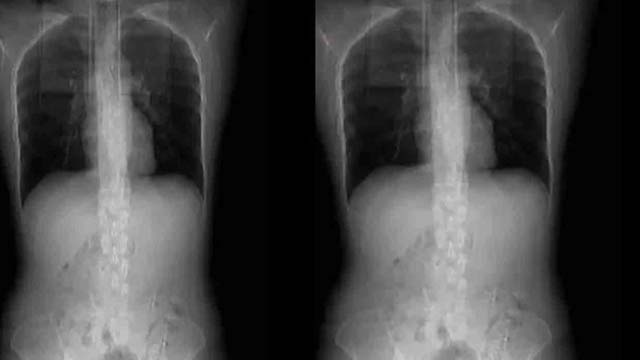

চল্লিশ বছর বয়সী এক নারী ঝাল খেতে গিয়ে রীতিমতো অসুস্থ হয়ে পড়েছেন। শোনা গেছে তিনি কোনো এক রেস্তরাঁয় খেতে যান। খাবারে ঝাল ছাড়াও নানা ধরনের মশলা ছিল। সেগুলো থেকে বেশ ঝাঁঝালো গন্ধ আসছিল। সেই খাবার খাওয়ার পরই কাশি শুরু হয় তার। আর সেটিই বিপদের কারণ হয়। টানা কাশতে থাকেন ওই নারী। এক সময় কাশির চোটে যন্ত্রণায় ছটফট করতে থাকেন। তখন তাকে হাসপাতালে নিয়ে যাওয়া হয়। চিকিৎসকরা পরীক্ষা করে দেখেন, তার পাঁজরের চারটি হাড় ভেঙে গেছে।

প্রথমত, দেখা যায় ওই নারীর ওজন স্বাভাবিকের তুলনায় বেশ কম। ৫ ফুট ৬ ইঞ্চি উচ্চতা হওয়া সত্ত্বেও ওজন মাত্র ৫৬ কেজি। এত কম ওজনের ফলেই বিপদ ডেকে এনেছেন তিনি। দ্বিতীয়ত, তার হাড়ের ঘনত্বও অন্যদের তুলনায় কম। ফলে কাশির চোটে তার বুকে আঘাত লাগে। আর সেটিই ভেঙে দেয় পাঁজরের হাড়।